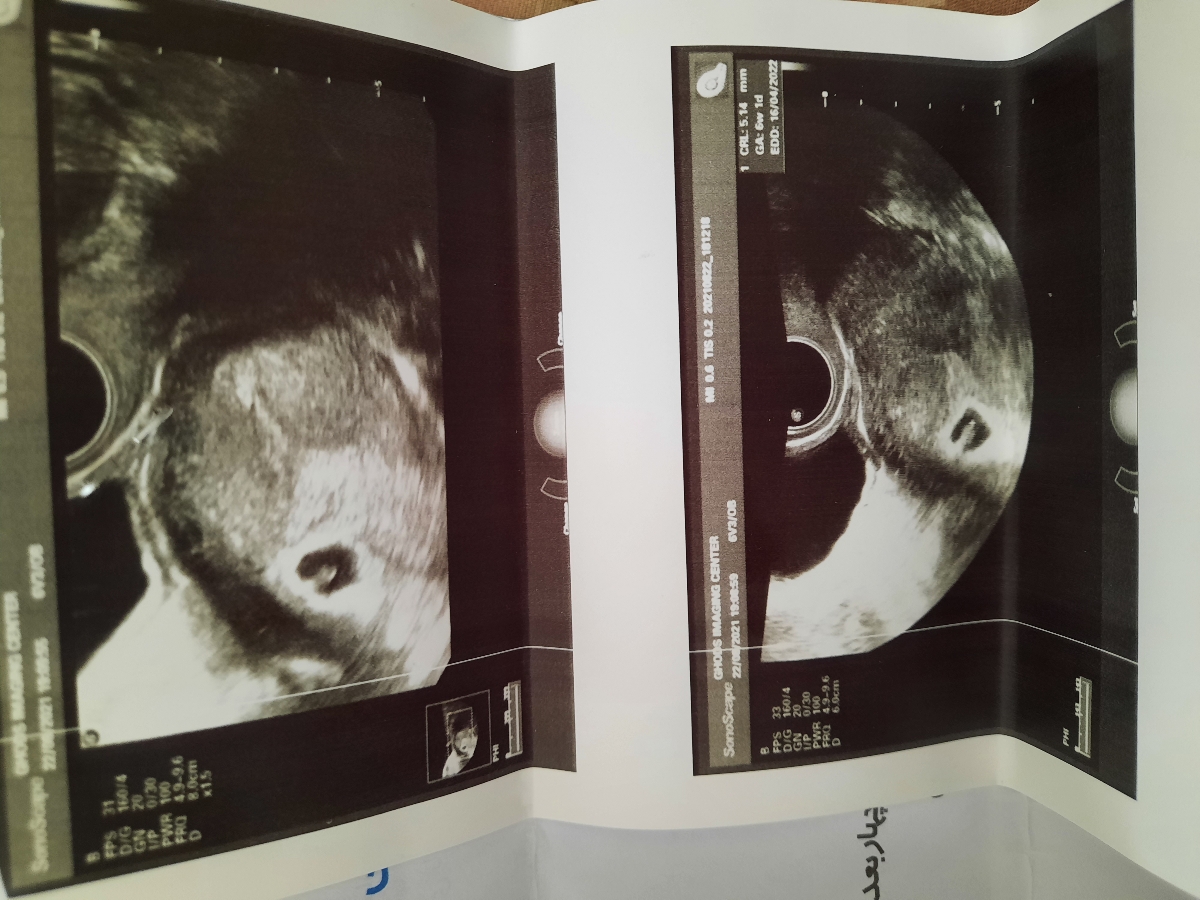

این عکس سونوگرافی

سلام ببخشیدمن دوشنبه سونوگرافی واژنیال انجام دادم ساک حاملگی بود ولی قلب جین تشکیل نشده بود